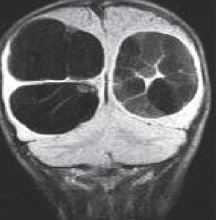

МРТ головного мозга. Корональная Т1-взвешенная МРТ. Многокамерные эхинококковые кисты.

![эхинококк головного]()